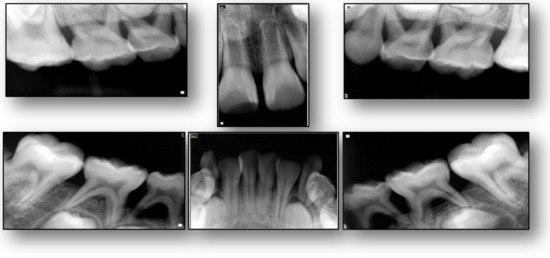

2. Case Presentation